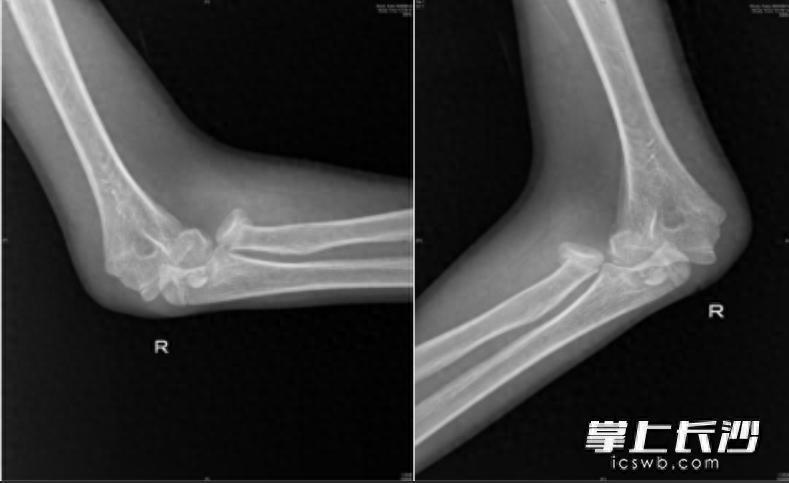

人体的肘关节就像一座精密的“协作工厂”,里面住着三位重要“伙伴”即桡骨、尺骨和肱骨。桡骨顶端有一个像“小圆帽”的结构,即桡骨头,它相当于肘关节的“旋转轴承”,帮助我们完成转笔、拧瓶盖、拧毛巾等需要前臂旋转的动作。当我们低头紧盯手机屏幕,不仅注意力高度集中,身体平衡能力也会下降,一旦不慎跌倒,手会本能地支撑地面。此时巨大冲击力会沿手臂向上传导,如同“冲击波”一般直击桡骨头这个“小圆帽”,轻则使其裂缝,重则崩碎成数块。通过X光片,医生可以清晰地看到它的“受伤模样”。